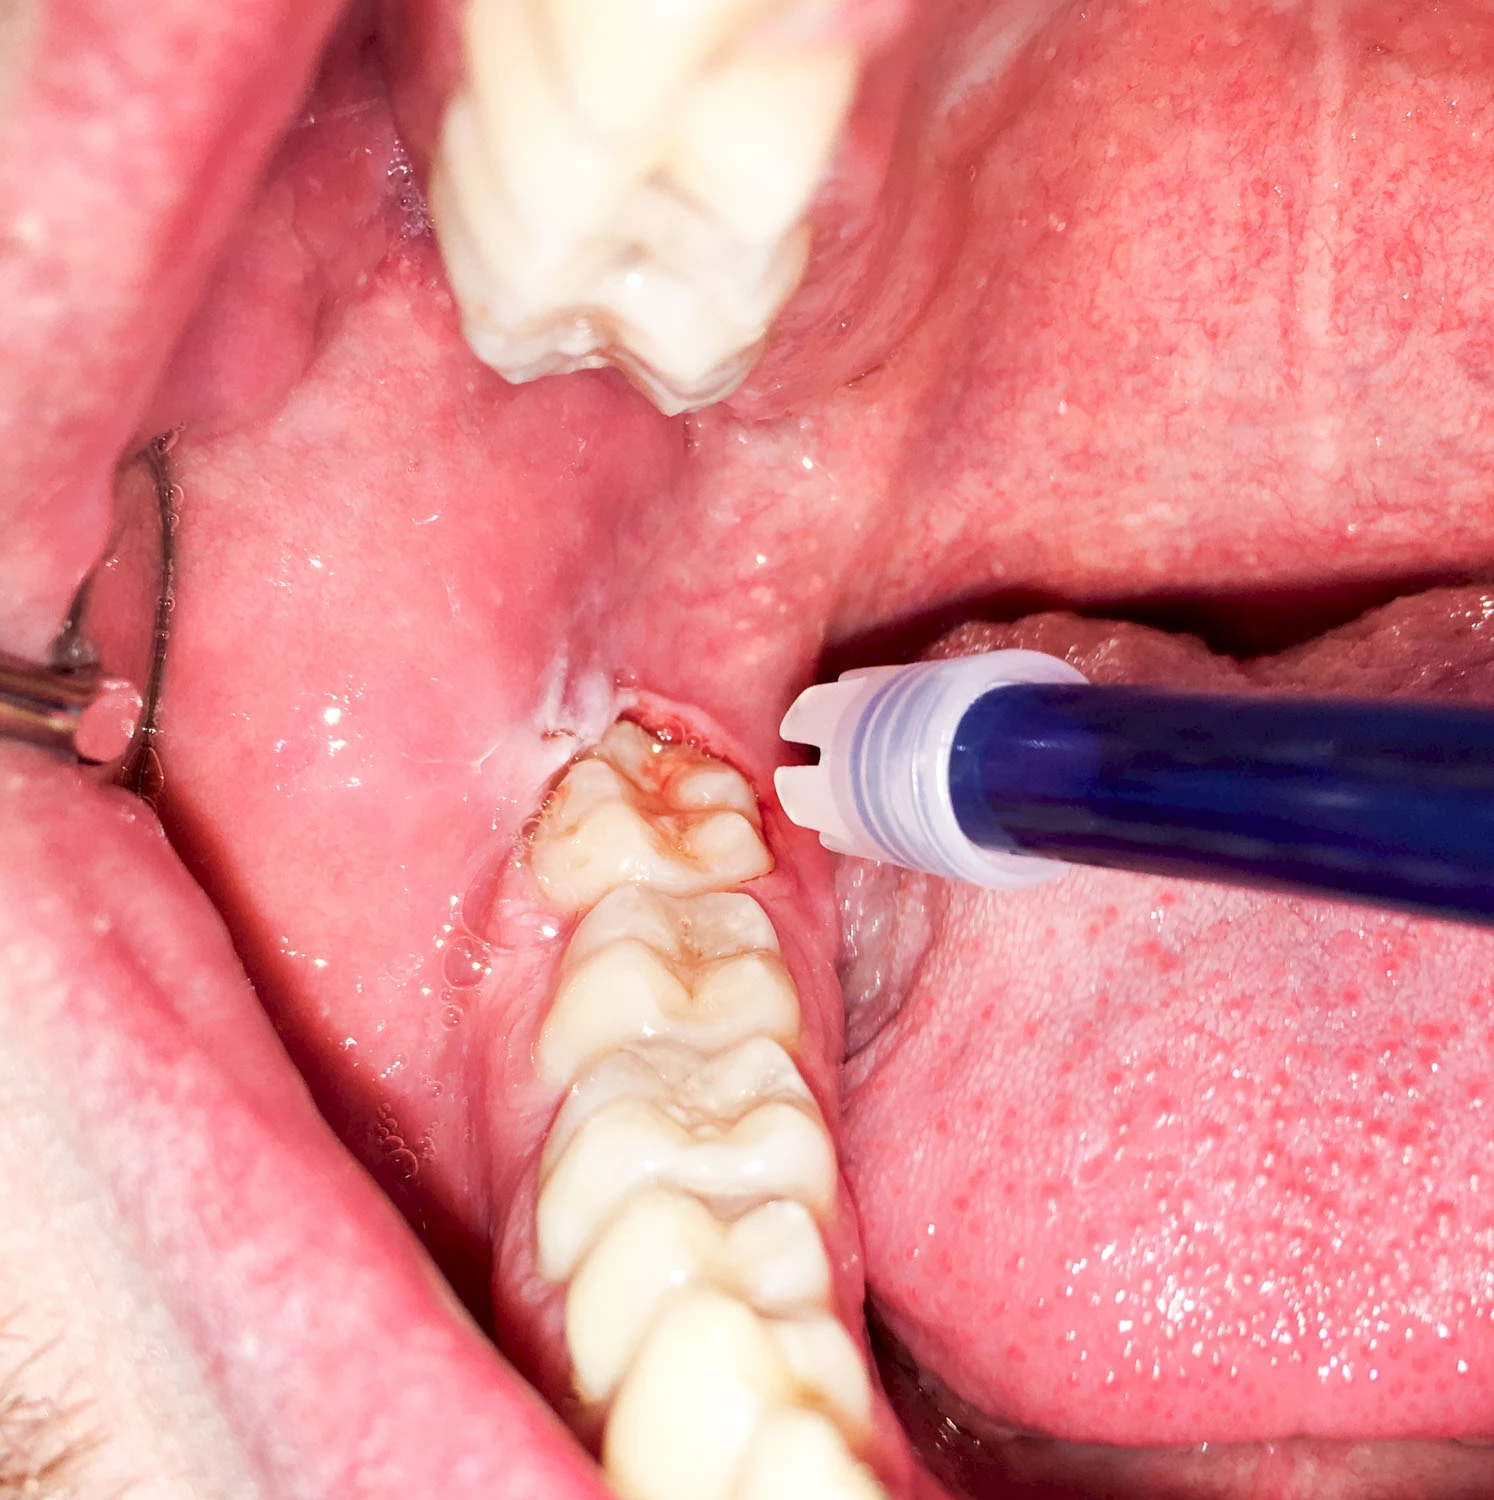

Sonderform: Schlupfwinkelinfektion

Im Laufe der menschlichen Entwicklung haben sich die Kiefer aufgrund unserer Nahrungsumstellung rückgebildet. Die Weisheitszähne haben daher oft keinen Platz mehr. Bei ca. 30 % der Menschen sind diese Zähne schon gar nicht mehr angelegt. Zum Teil liegen die Zähne versteckt (retiniert) im Kiefer und sind nicht sichtbar. Hin und wieder brechen die Zähne zwar durch die Schleimhaut, aber nicht vollständig – es handelt sich um einen erschwerten Zahndurchbruch (dentitio difficilis). Dann sind die Zähne noch teilweise bedeckt von einer "Schleimhautkapuze". Gehen hier Speisereste und Bakterien unter die Schleimhautkapuze kann sich eine sogenannte Schlupfwinkelinfektion bilden. Diese Entzündungen treten spontan auf, sind häufig sehr schmerzhaft und die Mundöffnung ist eingeschränkt. Hier ist umgehend der Zahnarzt zu kontaktieren.